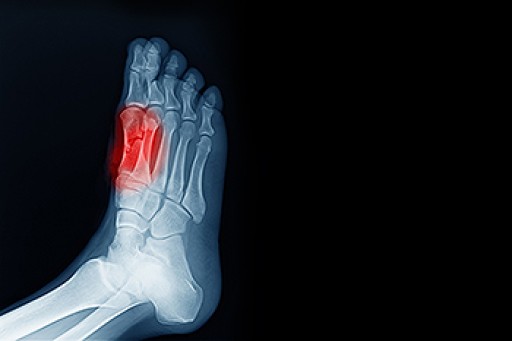

A sesamoid bone is independent, typically embedded in a muscle and connected to a tendon. There are sesamoids throughout the body such as the hands, wrist, feet, and kneecap which is the largest sesamoid. There are two sesamoid bones in the feet that are tiny, pea-shaped bones that are embedded in tendons in the ball of the foot. They are situated underneath the big toe joint. Repetitive stress in the ball of the foot can cause the sesamoids and the tendons in which they are embedded to become painful and inflamed. This condition is known as sesamoiditis. Although sesamoiditis can affect anyone, it often occurs in dancers and athletes who run and play tennis, basketball, and football. If you believe you may have sesamoiditis, consult with a podiatrist who can diagnose your condition through an examination and various imaging tests, and treat the condition using a variety of methods.

Sesamoiditis is a condition of the foot that affects the ball of the foot. It is more common in younger people than it is in older people. It can also occur with people who have begun a new exercise program, since their bodies are adjusting to the new physical regimen. Pain may also be caused by the inflammation of tendons surrounding the bones. It is important to seek treatment in its early stages because if you ignore the pain, this condition can lead to more serious problems such as severe irritation and bone fractures.